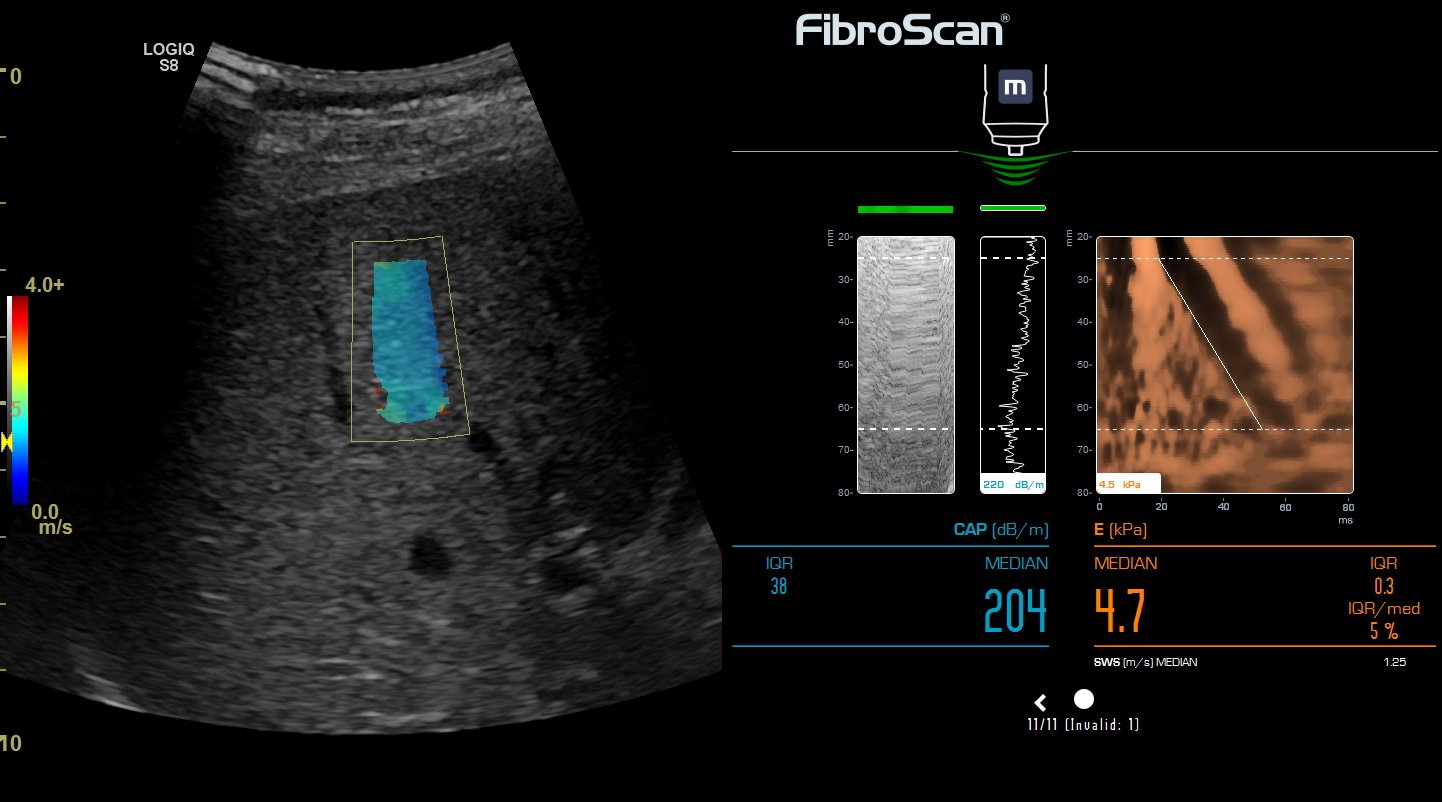

Эластометрия брюшной полости – это современный метод диагностики, который позволяет оценить состояние тканей органов в брюшной полости с помощью ультразвуковых волн. Это исследование помогает выявить различные заболевания на ранних стадиях, таких как цирроз печени, фиброз, воспалительные процессы и другие патологии, что способствует своевременному назначению эффективного лечения.

Эластометрия печени. Что выбрать: фиброскан или УЗИ?

Эластометрия печени. Что? Где? Когда?

Эластометрия печени. Покажет то, что не видно на УЗИ и в анализах.

Эластометрия - как метод мультипараметрического УЗИ. Большое интервью с доктором Пеняевой Э.И.